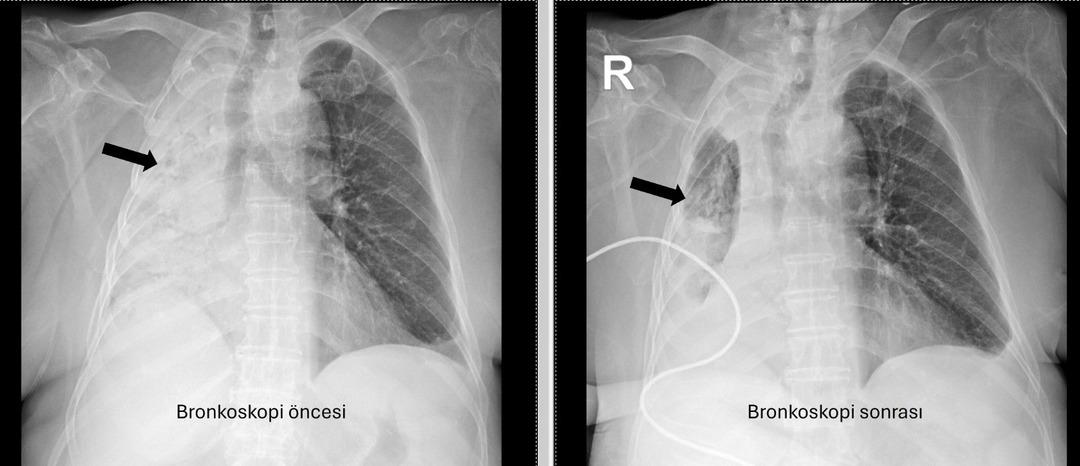

Denizli’de yaşayan 78 yıllık kadın ve emekli bir öğretmen yakın zamanda akciğer enfeksiyonu nedeniyle hastanede idi. 1 ay önce gittiği hastanede bronkoskopinin yapılmasına rağmen, sorunun tespit edilmediği öğrenildi. Yaşlı kadın, sağ akciğerin Pamukkale Üniversite Hastanesi’nin belirlenmesine tamamen kapatıldığı hastaneye gitti.

Pau Ökr Hastaneleri Göğüs Hastalıkları Bölümü. Prof.dr. Üye Dr.Köksel Altōiş Ergur, sağ akciğerler tarafından yapılan sınavlar için tamamen kapatıldı. Acil bronkoskopi planlandı ve prosedür derhal gerçekleştirildi. Dr. Altenishık ergur, hava yollarını incelerken çok yoğun ve karanlık bir salgılama ile esnek bir “bronkoskop” (esnek, katlanabilir), ancak hava yollarının derinlemesine temizlenmesini takiben, bir olaydan dolayı dönüştürüldüğünü ve berrak olduğunu, bir olaydan dolayı dönüştürüldüğünü açıkladığını açıkladığını açıkladığı açıktır. Vücudun açık olduğu açık olduğu açık olduğu açık olduğu açıktı. genel anestezi ile yapılmıştır;

Prof. Alküzek Ergur, hastanın trakeasının nasıl engellendiğini açıkladı: “Havayollarında sıvı emen aspiratörün gücünü kullanarak nesneyi çıkarmak mümkün oldu. Hastanın hastanın tekrar yediği pizzada yediği pizza için daha önemli olduğu öğrenildi.